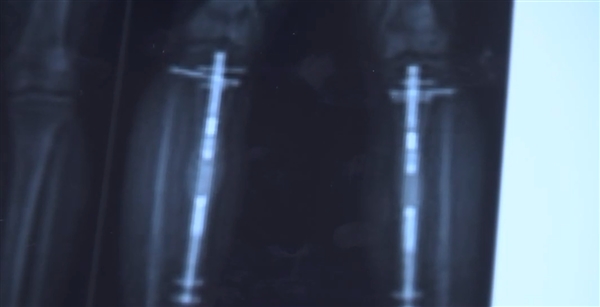

Kevin博士透露,简单来说,手术是将顾客的股骨(大腿骨)和胫骨(小腿骨)切断后找到中空处,接着植入一种特殊的拉伸装置并固定。

尽管手术全程不过1.5小时,可完全见效也就是所谓的永远长高(最多6英寸)则需要1年左右的时间。术后有两个重要环节,一是顾客需要每日使用体外遥控来操纵装置延长1mm,另外一点是需要2~4周做一次理疗训练。

对于第一项环节,Kevin解释,这是为了“欺骗”身体/他人以及你自己正在慢慢长高。一年后,体内的钉子会被移除,此时新的骨头和组织已经长好了。